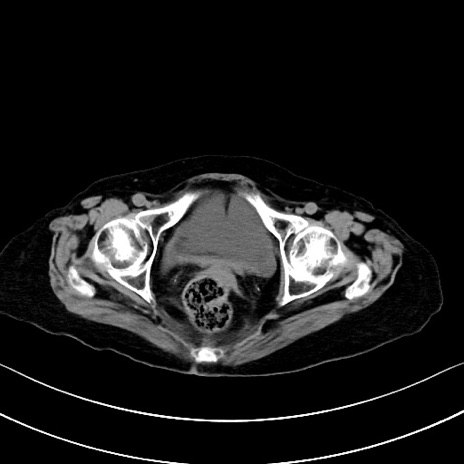

横断像

他院CT